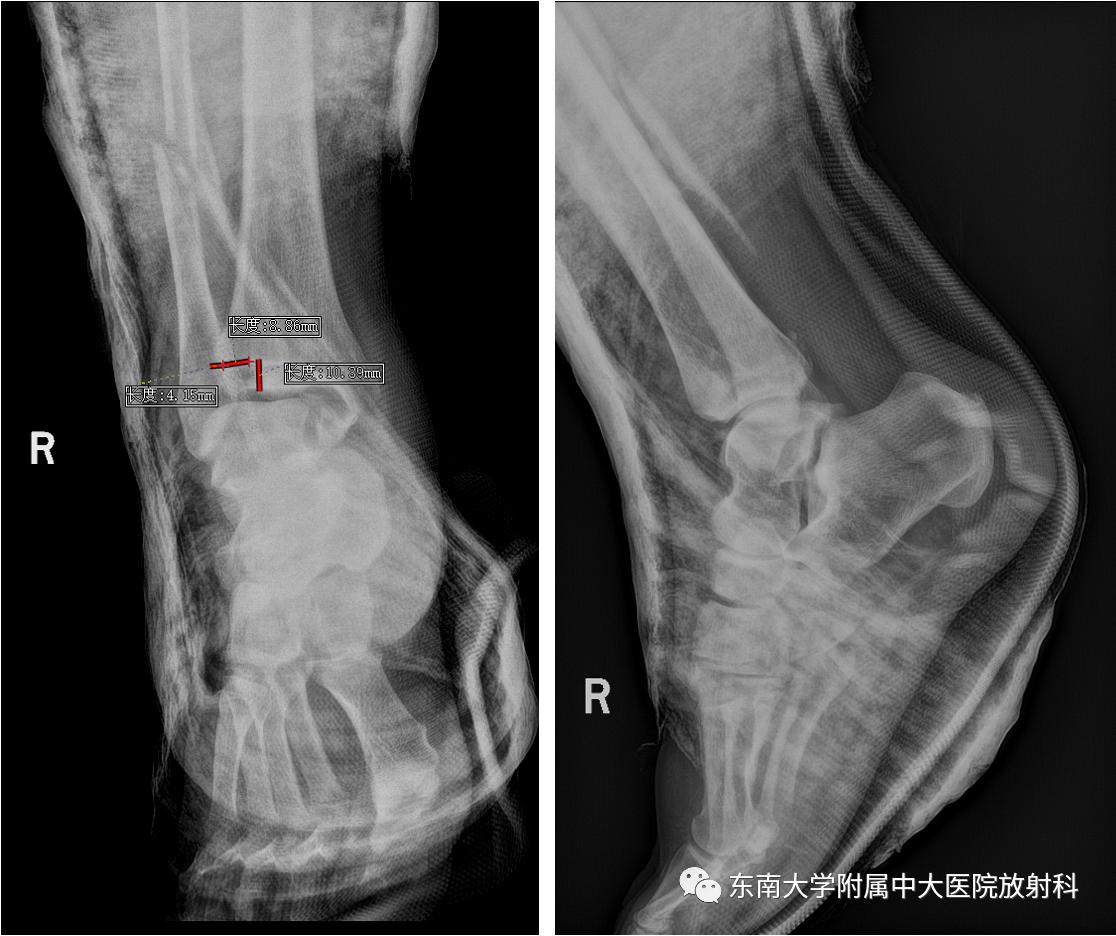

• 男,39岁

• 主诉:右踝部肿痛伴活动受限 10 小时余。

• 现病史:患者 10 小时前下楼梯踩空致右踝部疼痛伴活动受限,疼痛为胀痛,运动后疼痛加剧。各足趾活动可。

影像学表现